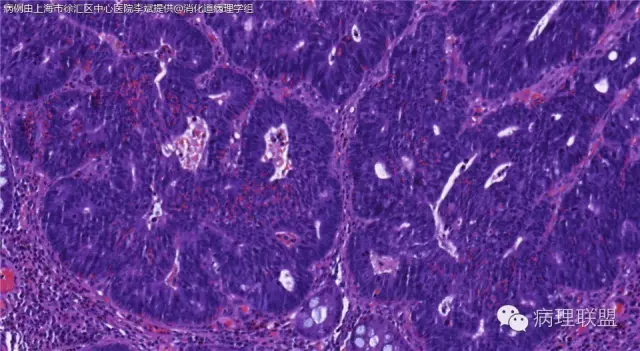

男,72岁,距肛门口30cm息肉。大体:灰白结节1.5*1*0.8cm拟发管状腺瘤并部分区高级别,请各位老师指导!(病例由上海市徐汇区中心医院 李斌 提供,致谢!)

这一例有两种不同看法,按WHO标准,为高级别,按实际工作,要发粘膜内癌。WHO第三版与第四版均提出,侵犯至粘膜下层才能诊断为癌,声称结直肠粘膜内没有淋巴管,发生转移的概率较小,但是粘膜内有血管,肿瘤侵出粘膜腺体基膜以外,就能侵犯血管,照样可以发生血道转移。文献报告与我们的工作实践,发现腺瘤、高级别(没有侵出基膜)的患者,同样有发生血道转移。因此,我们废弃了这一条WHO标准(不是所有的WHO标准都是一定要执行的)。只要异型增生腺体呈毛刺状、迷芽状侵出粘膜腺体基膜,位于粘膜肌层以内,就发粘膜内癌。

@李斌 结肠腺瘤这例我认为已经有黏膜下浸润了,因为有些腺体间的间质已经不是固有膜间质而是促结缔组织增生反应的间质了。但即使有浸润癌,如果息肉完整摘除、癌成分分化好、没有脉管瘤栓、浸润癌距切缘大于1mm(日本标准还要看浸润癌超出黏膜肌深度和肿瘤出芽情况),也不需要进一步治疗。所以,对于这类可能存在争议的病变,特别是息肉已经完整切除的病例,诊断的关注点就应该放在寻找需不需要进一步治疗的证据上了。@邓永键 2010版WHO在腺瘤部分的陈述中已经写出对于有局灶浸润性生长的病例也可以称黏膜内癌,他们在悄悄的让步。